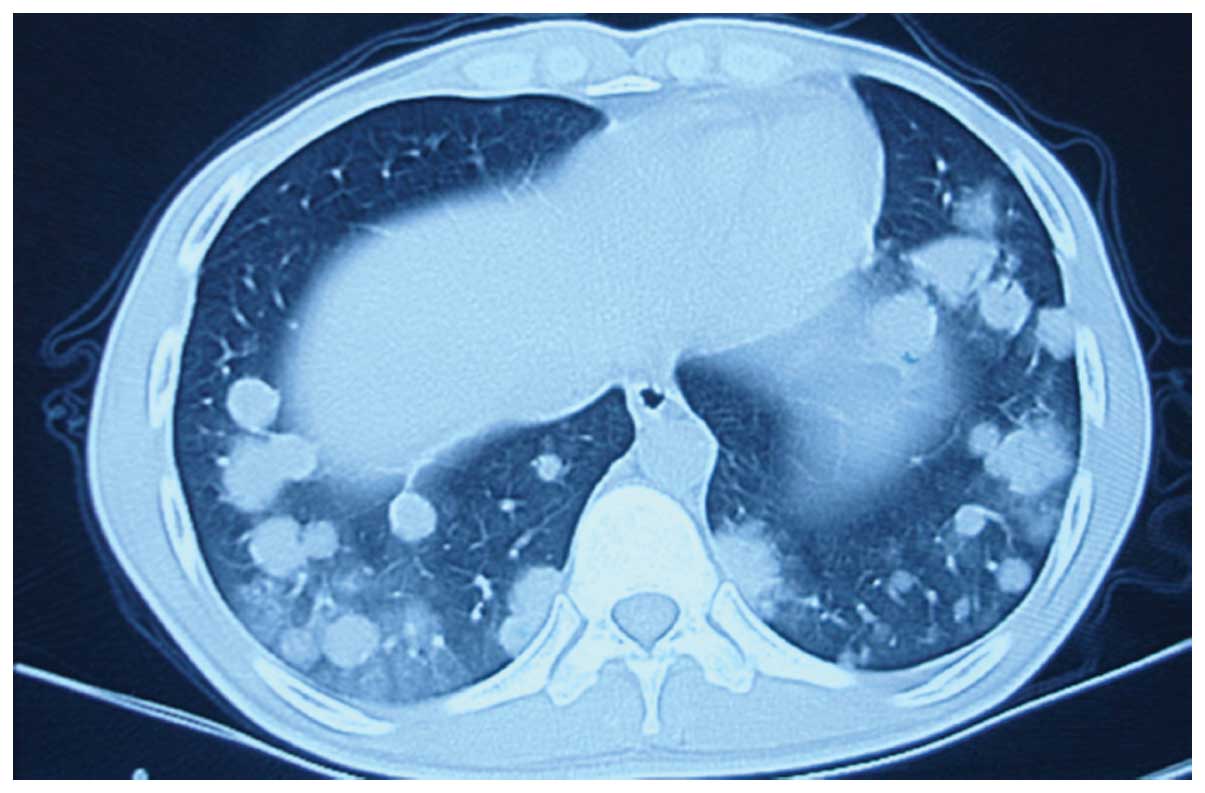

Lymphomatoid granulomatosis involving the central nervous system: A case report and review of the literature

Lymphomatoid granulomatosis (LYG) is a rare tumor with unknown etiology. Specific etiological factors for LYG are also unknown, although previous data indicates that LYG is an Epstein‑Barr virus‑associated B‑cell proliferation associated with an exuberant T‑cell reaction. According to the 2008 WHO classification, LYG is characterized by B‑cell proliferation of B‑lymphoma cells. Generally, treatment options for LYG are similar to those for diffuse large B‑cell lymphoma. Unfortunately, LYG is a chemotherapy‑resistant disease in certain patients and has a poor prognosis. The current study presents the case of a 19‑year‑old male patient with pulmonary LYG. The patient exhibited progressive disease following one cycle of chemotherapy with cyclophosphamide, adriamycin, vincristine and prednisone, and nodular lesions in the brain were diagnosed. Radiotherapy was delivered to the whole brain, however, this treatment did not prevent progression of the disease and the patient succumbed three months after initial presentation. An overview of the literature with regard to the etiology, clinical features, diagnosis and treatment options for LYG is also presented in the current case study.